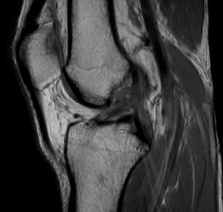

MRI Scan of a Knee

MRI has long been heralded as a reliable, non-invasive imaging modality for assessing soft tissue injuries. In many instances, it effectively elucidates complete ACL tears, characterizing the disruption of fiber continuity and associated findings like bone bruising. Yet, when it comes to partial ACL ruptures, the MRI narrative becomes more intricate.